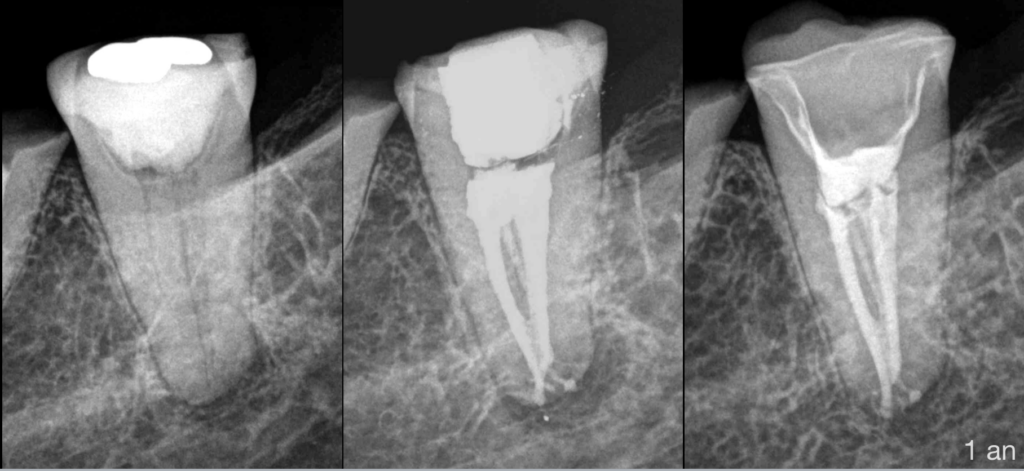

✨ 𝐀̀ 𝟏 𝐚𝐧 𝐝𝐮 𝐭𝐫𝐚𝐢𝐭𝐞𝐦𝐞𝐧𝐭, 𝐥𝐚 𝐜𝐢𝐜𝐚𝐭𝐫𝐢𝐬𝐚𝐭𝐢𝐨𝐧 𝐞𝐬𝐭 𝐞𝐟𝐟𝐢𝐜𝐚𝐜𝐞. ✨